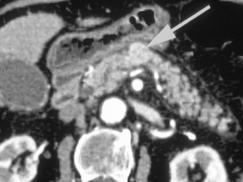

选项 A、典型症状是清晨自发性低血糖 B、是胰腺内分泌肿瘤中最常见的 C、绝大多数是恶性肿瘤 D、单发肿瘤占90%以上 E、给予葡萄糖或进餐后症状缓解

答案 C